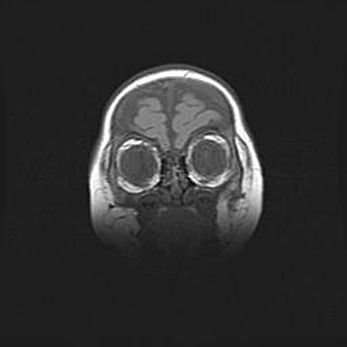

Наружная гидроцефалия с возможной атрофией височных областей.

Возраст: 28 дней

Вес: 3670 г

Пол: мужской

Окружность головы: 38 см

Срок гестации: 40 недель

Гидроцефалия головного мозга у новорожденных – это заболевание, которое характеризуется скоплением избыточного количества спинномозговой жидкости в желудочковой системе головного мозга в результате затруднения её перемещения от места выработки к месту поглощения в кровеносную систему или вследствие нарушения абсорбции. При открытой наружной форме гидроцефалии у новорожденных расширяются и переполняются субарахноидные пространства.

При нормотензивных  формах,  которые,  как  правило,  являются  следствием  перенесенных ишемических  повреждений  паренхимы  мозга,  возможно  сочетание микроцефалии  с нормотензивной гидроцефалией. В основе данных изменений лежит атрофия больших полушарий с преимущественной  локализацией  в  лобно-височных  областях.